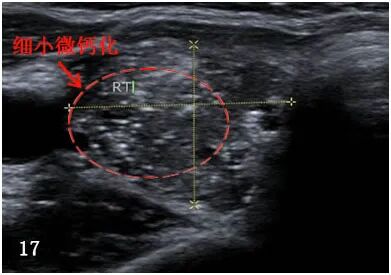

“微钙化”是点状强回声,无后部声影,直径 < 2 毫米,包括实性成分内的小彗尾征象(图 17)。 多为砂粒体聚集体,50%以上甲状腺乳头状癌结节内可见微钙化。

![图片[9]-一份甲状腺超声报告到手,从哪看起?-首码网-网上创业赚钱首码项目发布推广平台](https://mmbiz.qpic.cn/mmbiz_jpg/XsibUvKtQsKx2NNYO3iakSag8ODBKyawhY3nzibYbX2BmBPvbCgicwGKOfjld3NULQlBDOQBErzicOUgcP6WjgdwuIA/640?wx_fmt.jpeg)

资料来源:人力资源和社会保障部出版的《超声影像报告标准及数据系统分析》